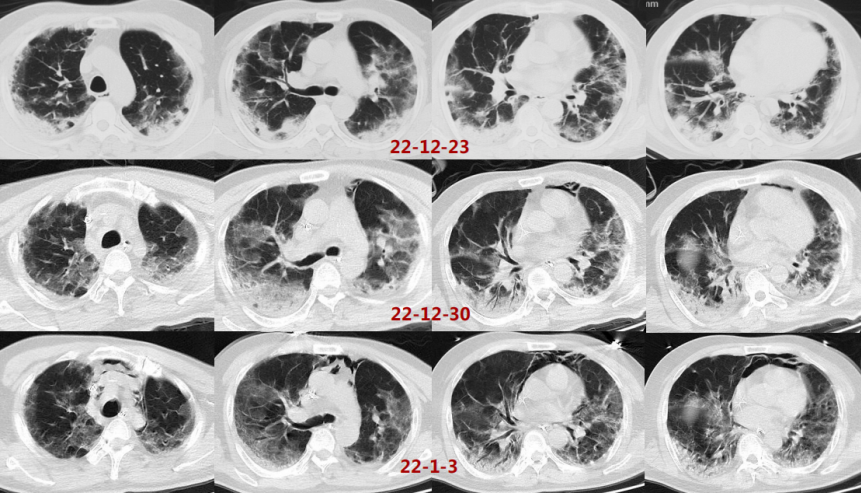

注:VV-ECMO参数:2700~3045 r/min,BF 3.4~3.9 L/min,GF 3 L/min,FiO2 1.0影像:下图分别是患者起病14、21及25天的胸部CT对比,在抗炎之后,患者肺部实变部分有明显吸收,且范围缩小。患者影像学变化过程:单纯磨玻璃影→实变伴磨玻璃影→实变、磨玻璃影伴牵拉性支气管扩张。综合上述,抗炎治疗后患者炎症指标下降、氧合改善、影像学吸收,综合判断抗炎治疗有效。患者在插管后出现了严重的酸中毒,在增加分钟通气量后,仍难以改善高碳酸血症和低氧,故选择ECMO支持。插管后3天,为了加强气道管理予气管切开。在ECMO支持7天后,复查胸部CT发现少量纵隔气肿,故于当天下调PEEP至6 cmH2O。追溯患者发生气压伤的原因,可能与过高的呼吸驱动有关,上调瑞芬太尼和丙泊酚的泵入速度,加深镇痛镇静。2023年1月1日患者PaO2较前稍有下降,查体双肺湿啰音,无皮下气肿及气胸表现,所以再次上调PEEP至8 cmH2O。经过上述处理,患者呼吸频率仍在25次/min左右,潮气量约为500 ml。1月3日患者出现寒战,ECMO抖管,再次复查胸部CT发现纵隔气肿较前加重,下调PEEP至4 cmH2O。在瑞芬太尼镇痛基础上应用丙泊酚+咪达唑仑双联镇静,患者呼吸频率下降,维持在20次/min左右,潮气量降至400 ml。